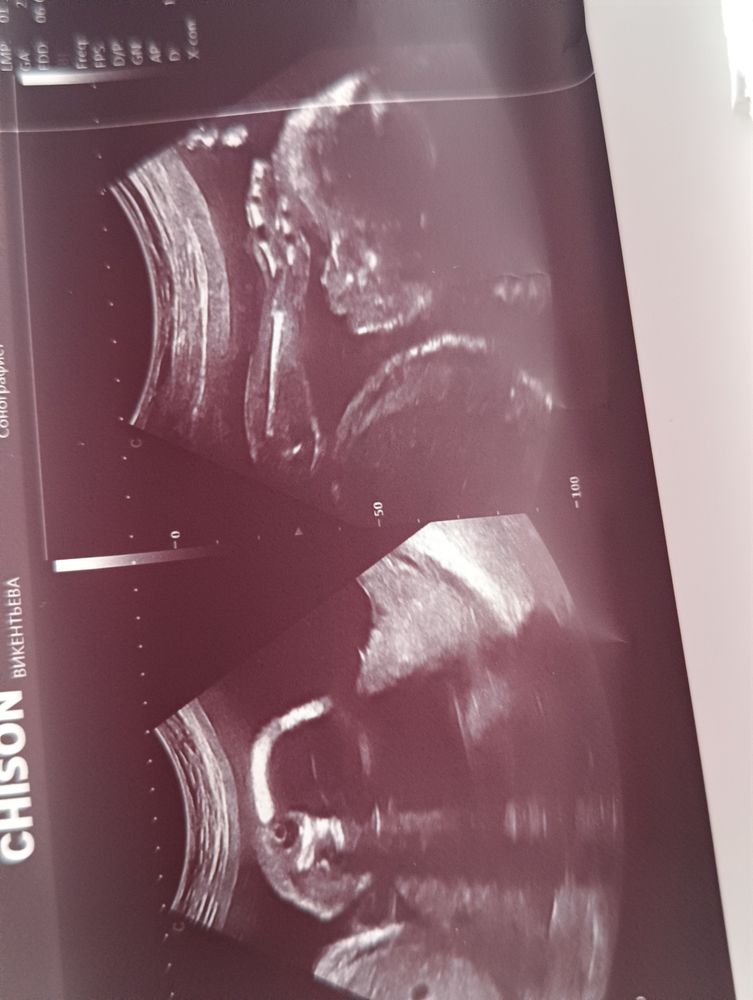

23+4 недельки.... УЗИ)

Срок бНе выдержала я и сгоняла на УЗИ, так хотелось малявку глянуть все ли хорошо, чистые воды ли и шейка длина норм ли ... Ещё раз пробежаться нет ли патологий.. в этот раз узист все пальчики даже пересчитал на ножках, ручках.. ещё сердечко посмотрел , голову....

На УЗИ даже глазки открыл малявка наша..весим 682 гр на 24 недели..сказали все в срок...148 уд / мин сердечк

Длина шейки матки 42 мм ..